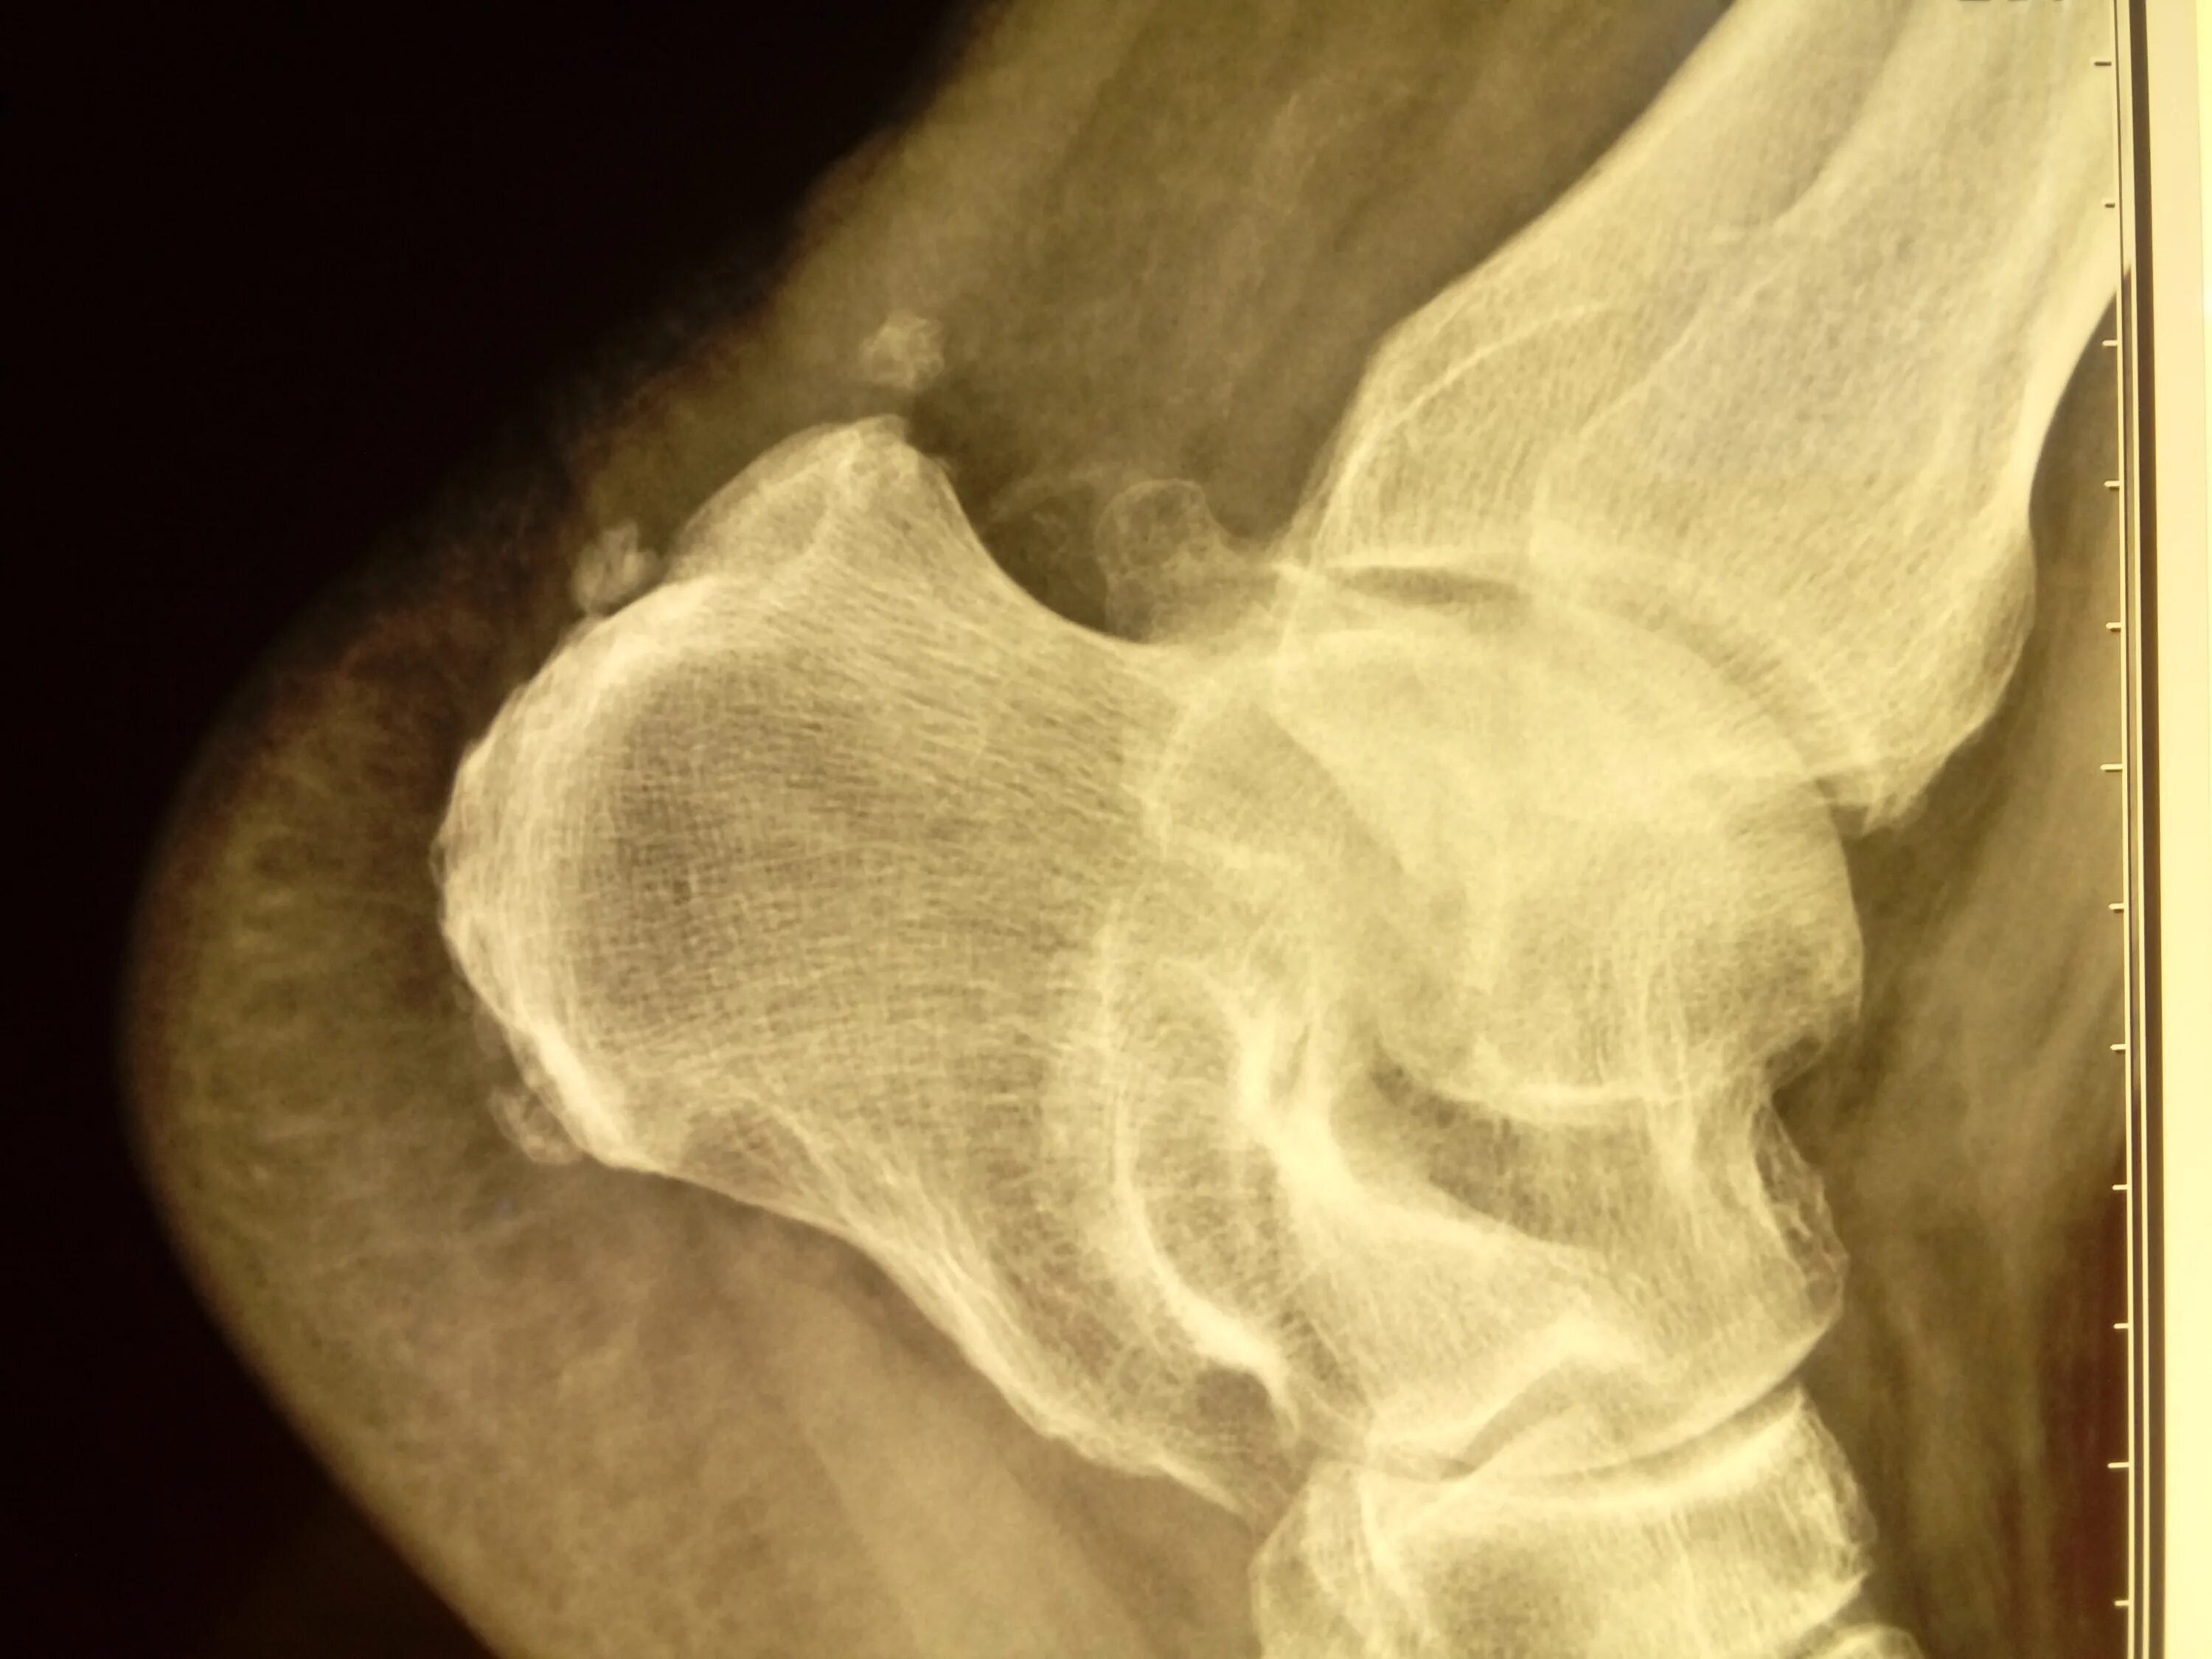

Болезнь шинца мкб 10